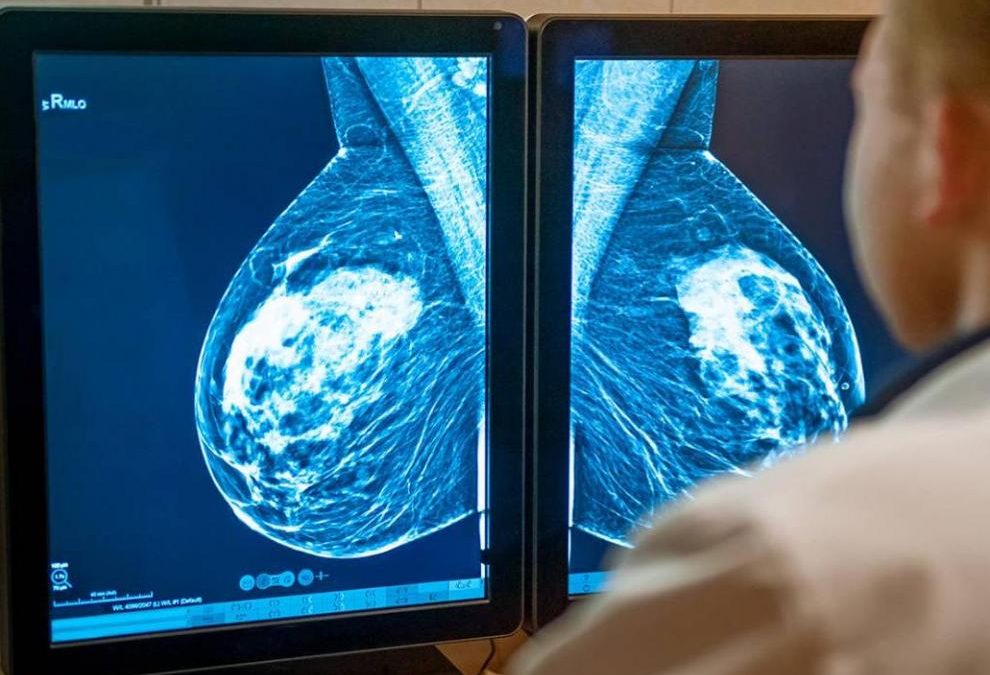

El Hospital Universitario Miguel Servet de Zaragoza participará en el estudio CAILA, para buscar una alternativa al tratamiento de cáncer de mama avanzado resistente a la terapia endocrina.

Con 32.953 nuevos casos diagnosticados en 2020, el cáncer de mama es el tipo de tumor más diagnosticado en España en mujeres. Se trata de una enfermedad heterogénea con múltiples cuadros clínicos y subtipos tumorales diferentes.